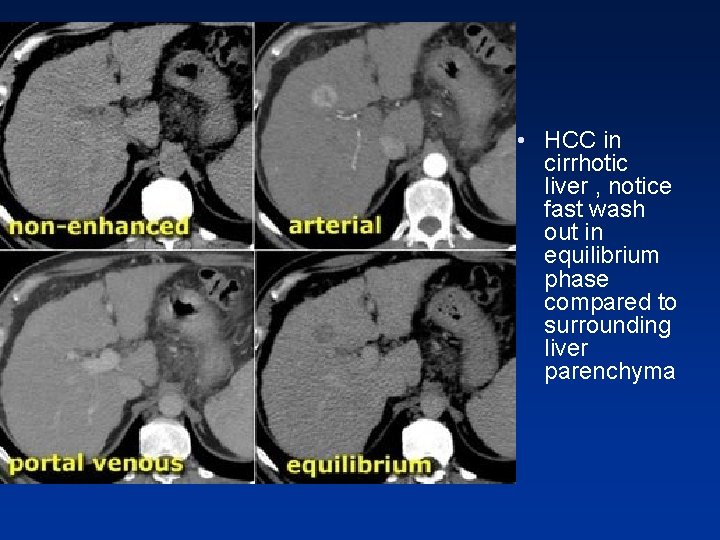

• HCC in a cirrhotic liver. Notice fast wash out in equilibrium phase compared to surrounding liver parenchyma.

• HCC in cirrhotic liver , notice fast wash out in equilibrium phase compared to surrounding liver parenchyma